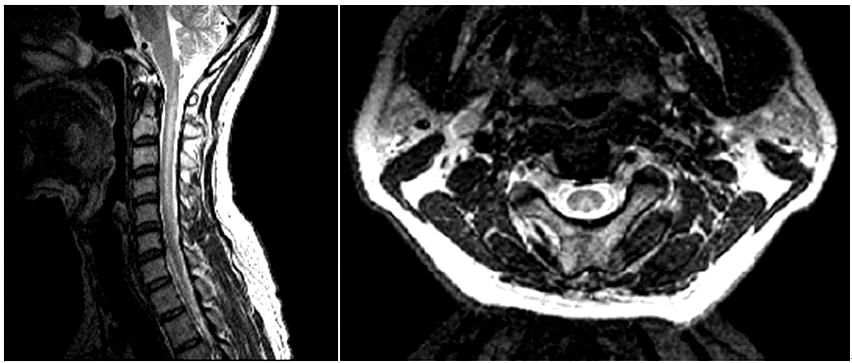

예) 65세 남자. 4개월 전부터 시작된 보행장애와 사지 저린감 - SCD